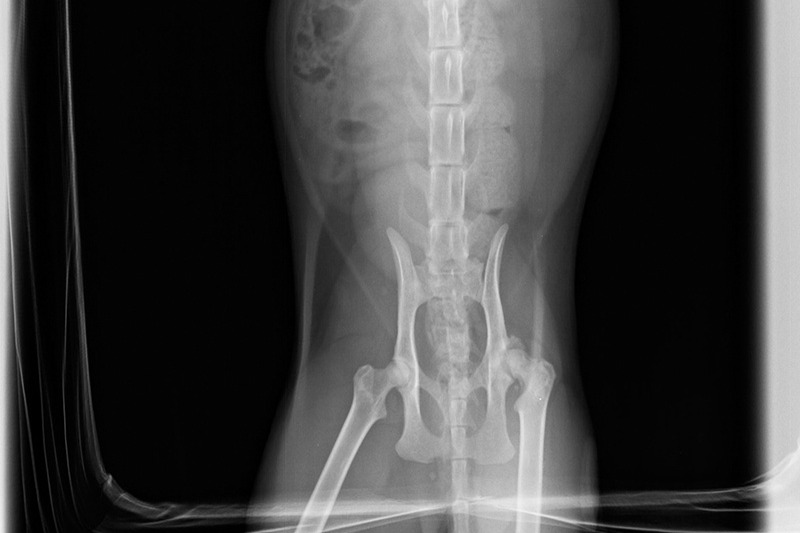

When I took him back to the vet for his booster shots, I asked them to X-Ray his hip to see if it was an injury or a congenital condition. They gave me the bad news that it was a defect in his hip which was going to keep getting worse until it could be corrected with surgery. I could afford a couple of hundred dollars here and there for normal vet expenses, but I'm a gig worker, and COVID took all my gigs away. There was no way I was going to be able to come up with a few thousand any time soon. Now, several months have gone by, and Ziggy no longer follows me around the house. The poor little guy can barely walk anymore, and although I have finally started getting work again in the last few weeks, I am nowhere near on an even keel yet, and Ziggy can't wait any longer.

Below are Ziggy's X-Rays- The first set was taken when I first got him in October. The others were taken three months later. I don't really know how to read them, but the vet said they could see noticeable deterioration in that short time: